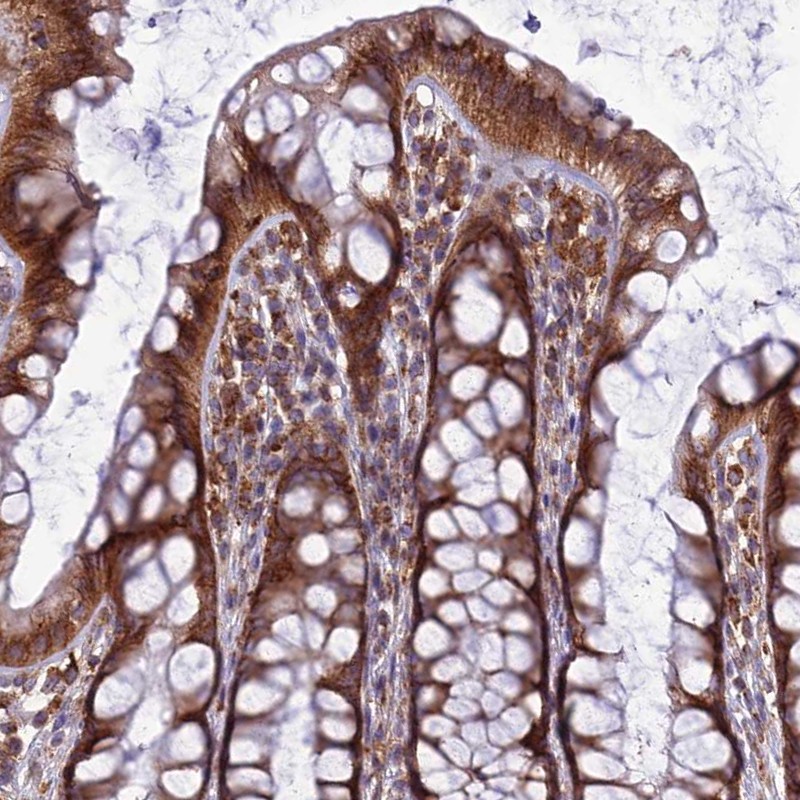

Immunohistochemical staining of human rectum shows strong cytoplasmic positivity in glandular cells.